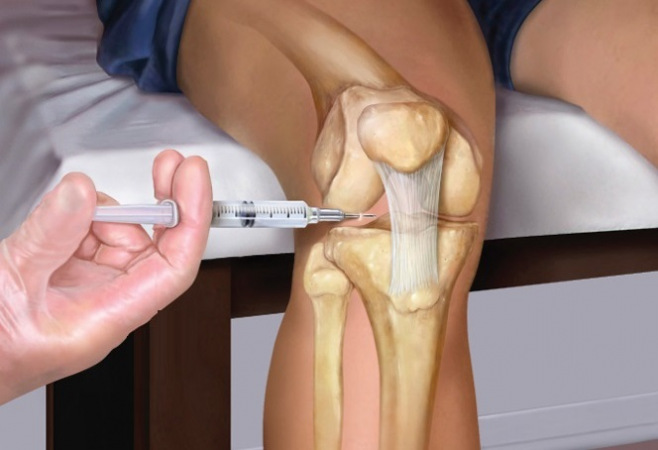

अपने जोड़ो को ठीक करने में कैसे मदद करें मैं एक अनूठे दृष्टिकोण का उपयोग करता हूं, जो न तो दर्द को दबाने पर केंद्रित होता है, बल्कि जोड़ो को फिर से ठीक करने और उनके नष्ट होने के कारणों को समाप्त करने पर है। जर्मनी में हम पहले से ही उन तरीकों का उपयोग कर रहे हैं जो जोड़ो में रक्त संचार को बहाल करते हैं और जमा हुए नमकों को समाप्त करते हैं। यह न केवल दर्द को कम करने में मदद करता है, बल्कि जोड़ के पुनर्निर्माण की प्रक्रिया को भी शुरू करता है।

मेरे उपचार के बाद, राजेश ने कुछ सप्ताहों में महत्वपूर्ण सुधार महसूस किया। उसके जोड़ बिना दर्द के हिलने लगे और वह पहले जैसा विकलांग नहीं महसूस कर रहा था

Biotrin एक ऐसा पदार्थ है जो अपनी प्रभावशीलता साबित कर चुका है और जिसे मैंने राजेश को सिफारिश की थी। इस पदार्थ में कई प्राकृतिक तत्वों का एक संपूर्ण परिसर है, जो न केवल लक्षणों को कम करने में मदद करते हैं, बल्कि जोड़ो के सामान्य कार्य को फिर से बहाल करते हैं। Biotrin में क्वीविटामिन बी शामिल है, जो जोड़ो की स्थिति को सुधारने और दर्द से छुटकारा पाने में सक्रिय रूप से काम करता है।